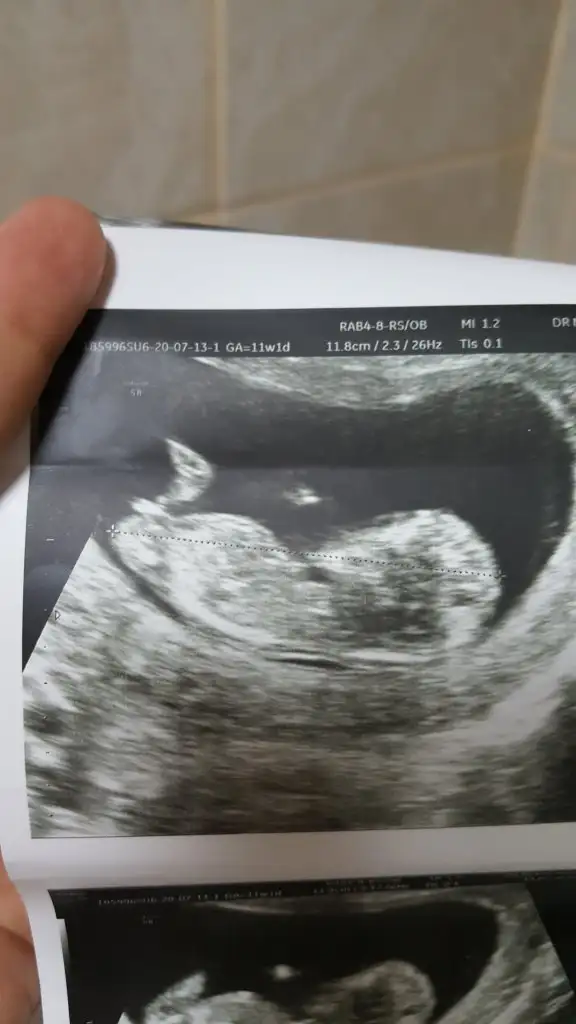

Bi bakabilir misiniz 12+6 oldukdr göremedim dedi.yorumlayabilirmisiniz

12+6 haftaKaç haftalık sanki erkek gibi geldi başka usg varsa paylaşın az yan pozisyonda minnoş![]()

Dr bir tek bunu verdi maalesef teşekkürler cvp içinKaç haftalık sanki erkek gibi geldi başka usg varsa paylaşın az yan pozisyonda minnoş![]()